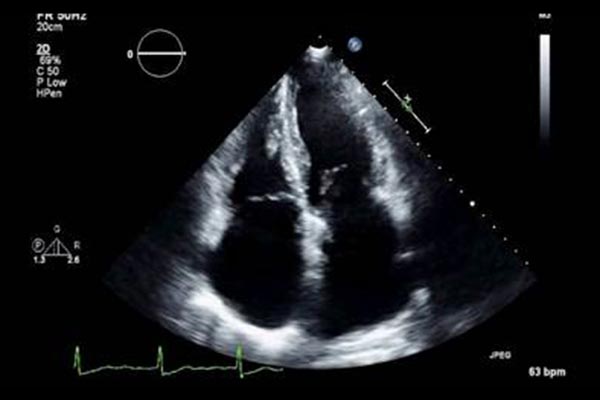

The Centre for AI, Data Science, and Imaging is redefining how cardiac care is delivered by combining cutting-edge artificial intelligence, advanced imaging, and data sciences to improve the diagnosis, treatment, and prevention of heart disease across British Columbia and beyond.

A patient’s geographical location should not determine the quality of care they receive. Through the use of AI and remote imaging technologies, the Centre strives to reach underserved communities, from rural and remote regions to long-term care homes and marginalized urban populations. With these tools, the earlier detection of heart disease, support for clinical decisions, and personalized care based on a patient’s genetics, imaging results, and environment are made possible.

The Centre’s team is passionate about understanding the heart and how its size, shape, function, stiffness, and contractility, combined with genomic and environmental data, can predict the risk for heart attacks, stroke, and arrhythmias. With this insight, clinicians can intervene earlier and tailor care more effectively. It has the talent, data, infrastructure, and visionary leadership to make this future a reality.